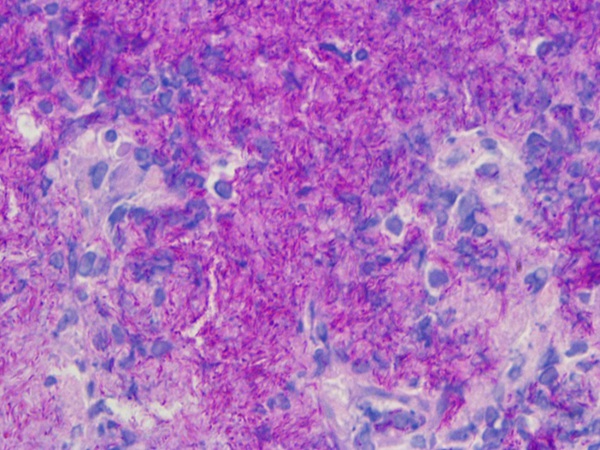

Ovaj set otopina za bojenje otpornih na kiseline prikladan je za otkrivanje bakterija otpornih na kiseline u tkivima. Nakon bojenja, jezgre su bile plave, a kiselootporne bakterije ljubičasto crvene.

Bakterije otporne na kiselinu su ljubičastocrvene s plavim jezgrama.